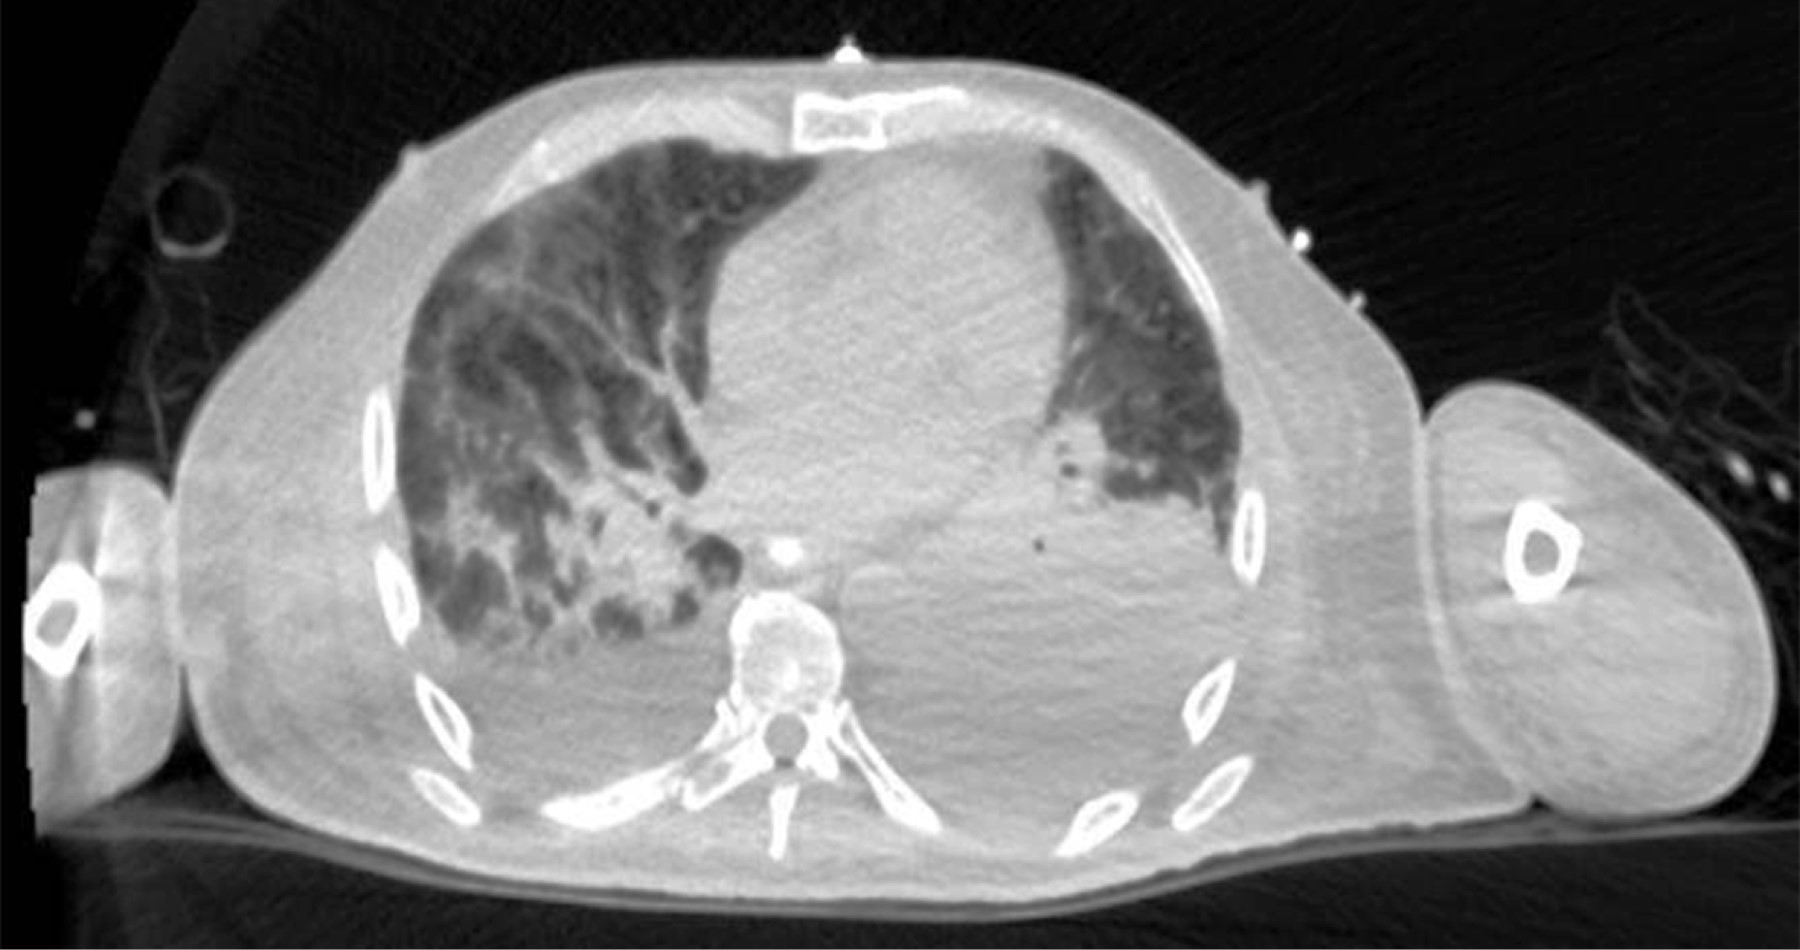

A 69-year-old male patient with a history of type 2 diabetes mellitus was treated with metformin and chlorpropamide. He also had hypertension treated with losartan and amlodipine. He presented to the emergency department with headache, chest pain, cough, myalgias, arthralgias, and dyspnea of one-week evolution. On admission, his heart rate was 114 bpm, respiratory rate 24 rpm, oxygen saturation 80% without supplemental oxygen support; his glucose was 587 mg/dl, white blood cells 25,690 cells/mm3, neutrophils 85%, lymphocytes 1.2%, hemoglobin 16.3 g/dl, procalcitonin 3.78 ng/dl, arterial blood gas with a pH of 7.41, pCO2 21 mmHg, PO2 35 mmHg, HCO3 13 mmol/l, oxygen saturation 62%. A rapid antigen test for SARS-CoV-2 was performed, and the result was positive; a CT scan of the chest showed radiological data suggestive of SARS-CoV-2 infection (Figure 1), and management with supplemental oxygen, insulin infusion pump, carbapenem antibiotics, antihypertensives, dexamethasone, and antithrombotic prophylaxis with enoxaparin was started. 48 hours after admission, the patient continued with septic shock, so vasopressor amines were started; an orotracheal intubation was performed and support with invasive mechanical ventilation was initiated. A nasogastric tube (NGT) was placed. After 24 hours of its placement, he presented hematemesis accompanied by abdominal distension, leukocytosis of 40,000 cells/mm3. A simple abdominopelvic CAT scan was performed, which revealed gastric pneumatosis and pneumoperitoneum (Figure 2). An urgent exploratory laparotomy was performed finding necrosis of the greater curvature of the stomach. A vertical gastrectomy was performed with GIA stapler with purple cartridges of 45 and 60 mm (Figure 3); the stapling line was reinforced with continuous a Prolene suture 00; a feeding jejunostomy tube was placed at 60 cm from the Treitz angle and Saratoga drains were left in place. Twenty-four hours later, the patient had hemodynamic stability, vasopressor amines were suspended, and enteral nutrition with an elemental diet was started. On the fifth postoperative day, the patient showed adequate tolerance to the enteral diet through jejunostomy. The methylene blue test was performed through the nasogastric tube showing no evidence of leaks; the white blood cell count decreased to 24,000 cells/mm3. Histopathology results were obtained revealing pan mural necrosis associated with arterial thrombosis secondary to microorganisms compatible with Mucor sp.; therefore, management with amphotericin B was initiated (Figures 4 and 5). During follow-up he showed good evolution; an abdominopelvic CT scan with contrast by the nasogastric tube was performed, which ruled out leaks and intra-abdominal collections and corroborated the integrity of the gastric wall; drains were removed, and the patient was discharged from general surgery on day 9 post-surgery, continuing to be managed by the internal medicine service. During the following days of hospitalization, the patient presented cardiovascular and pulmonary deterioration; a urine culture was taken, which showed growing of Candida tropicalis, and a CAT scan of the skull, thorax, and abdominopelvic with oral contrast was performed (Figures 6 and 7), The patient continued without evidence of abdominal leaks, rhino-cerebral and pulmonary mucormycosis were ruled out. A probable superimposed bacterial pneumonia and interstitial pneumopathy secondary to COVID-19 were reported. He showed persistent clinical deterioration and refractory shock and 29 days after admission.

On admission, the patient did not report any abdominal symptoms, so gastrointestinal involvement was not suspected. Subsequently, intravenous sedation and orotracheal intubation were performed, making it impossible for the patient to manifest gastric involvement. The only sign the patient presented was hematemesis 24 hours after the nasogastric tube placement, which ruled out the possibility of healthcare-associated mucormycosis since 24 hours are not enough to achieve the introduction, inoculation, and growing of the fungus. This led to the hypothesis that the patient acquired the fungal infection in his community. The diagnosis may be suspected by endoscopic findings, such as a fungal mass or necrotic lesions covering ulcerated areas that may perforate tissues and cause peritonitis.2 Often, the study protocol is initiated in the presence of an intra-abdominal abscess; the diagnosis can be made by biopsy of the suspicious area during surgery or endoscopy.7 Few samples are usually sent for culture,2 and those sent are positive in only 30%, in addition, specialized culture media such as potato dextrose agar are required for fungal growing.12 Confirmatory molecular tests that may detect surface antigens are also required, but they are not yet available.2 CT findings may include focal or diffuse thickening of the gastric wall, pneumatosis with decreased wall enhancement on contrast administration (emphysematous gastritis) secondary to ischemia and necrosis, adjacent collections, wall necrosis with focal disruption or perforation, and rarely, pneumoperitoneum.13 When hematemesis occurs, the next diagnostic step should be an upper endoscopy. However, the abdominal distention presented by the patient suggested a high probability of perforation of the hollow viscera, so initially, a CT scan of the abdomen was performed. A surgical emergency was considered when reporting gastric pneumatosis and pneumoperitoneum, ruling out an endoscopy. Exploratory laparotomy allows direct exploration of the stomach and partial resection of the stomach as a diagnostic and therapeutic measure. Treatment consists of antifungal and urgent surgical debridement since necrotic tissue's presence will affect the antifungal's penetration to the tissues; additionally, aggressive medical support for comorbidities should be provided.14 Intravenous liposomal amphotericin B is the treatment of choice. It is more effective than conventional amphotericin B.15 Delaying the initiation of amphotericin for more than six days, doubles mortality.4 Although most of literature favors aggressive surgical treatment, we opted for a more conservative treatment by preserving a portion of the stomach and performing only a vertical gastrectomy since macroscopic inspection showed a clear demarcation between necrotic and viable tissues. We consider that the surgical treatment we performed was correct since, in the post-surgical follow-up, the patient had a good evolution; the methylene-blue test and the two abdominal CT scans with contrast in the stomach through the nasogastric tube allowed us to verify the integrity of the suture line from the first post-surgical day until the day of his death. The sample sent to pathology allowed to make the diagnosis and thus initiate targeted therapy with amphotericin B, and since no fungal infection by Mucor sp. at any other organic level was found, the cause of death was attributed to nosocomial infectious complications at the pulmonary and urinary level.

Figure 6

Figure 7